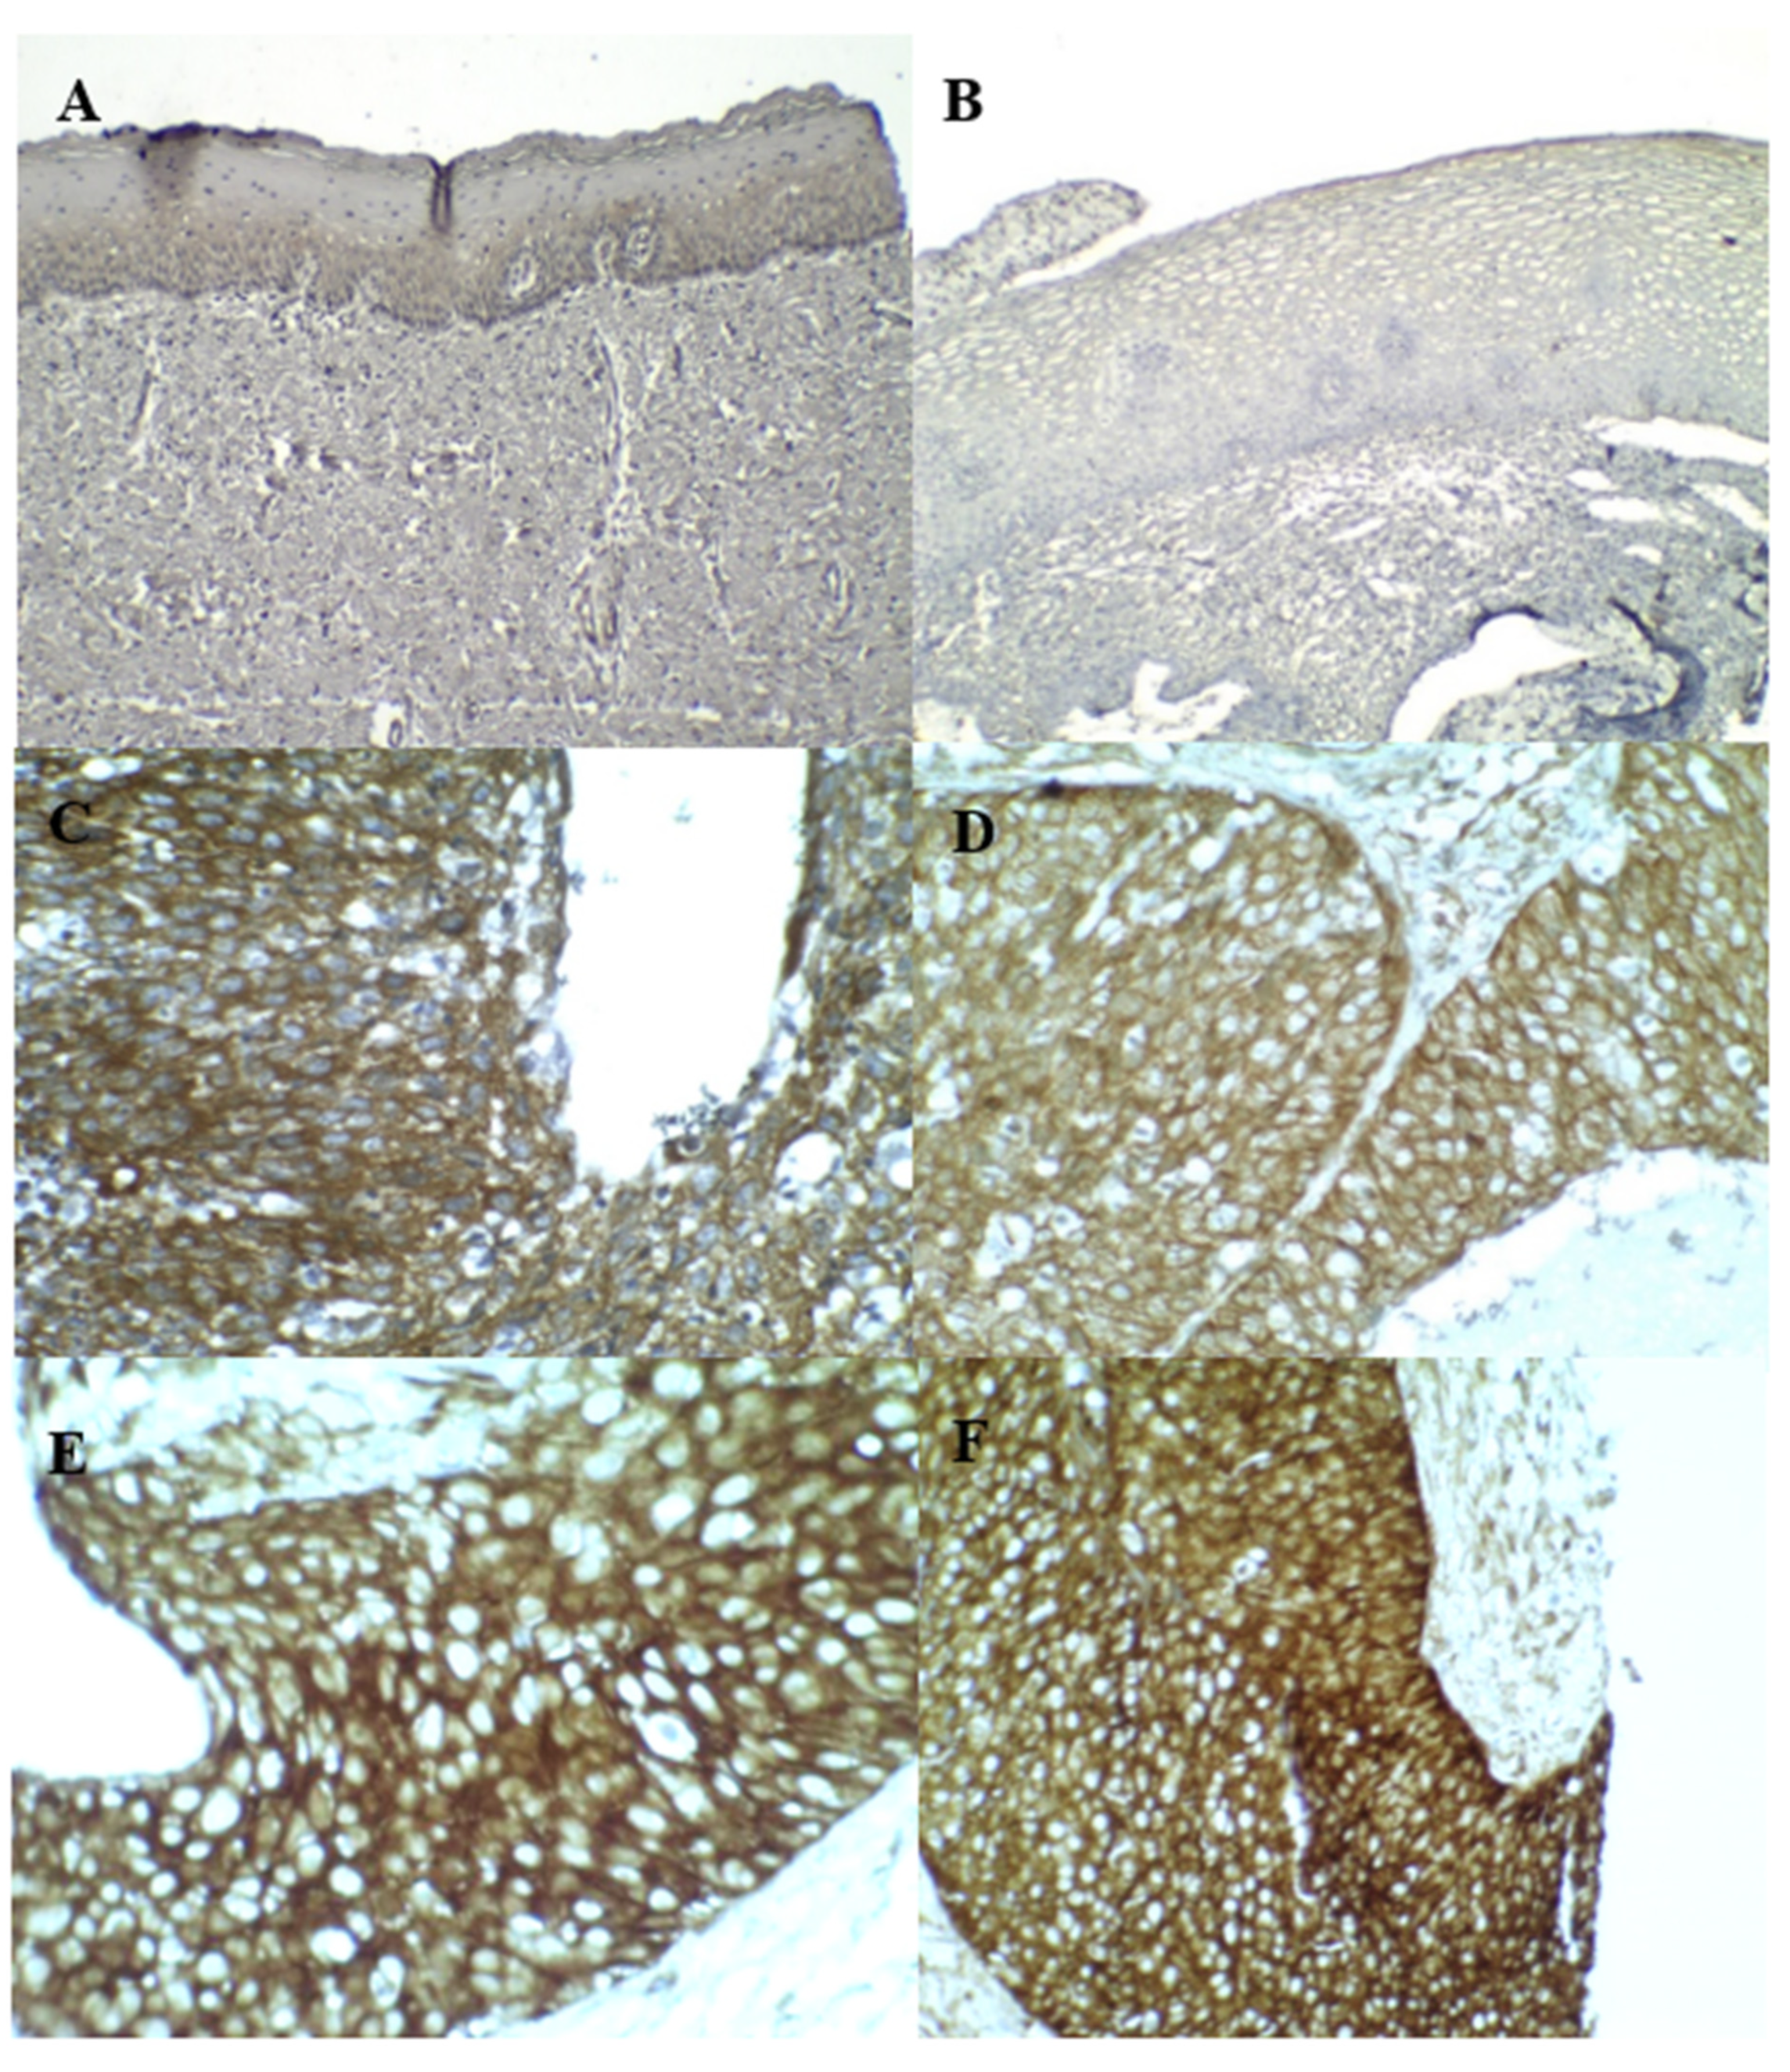

3.3. p16INK4A and Ki–67 Immunostaining

3.4. Cortactin Immunostaining